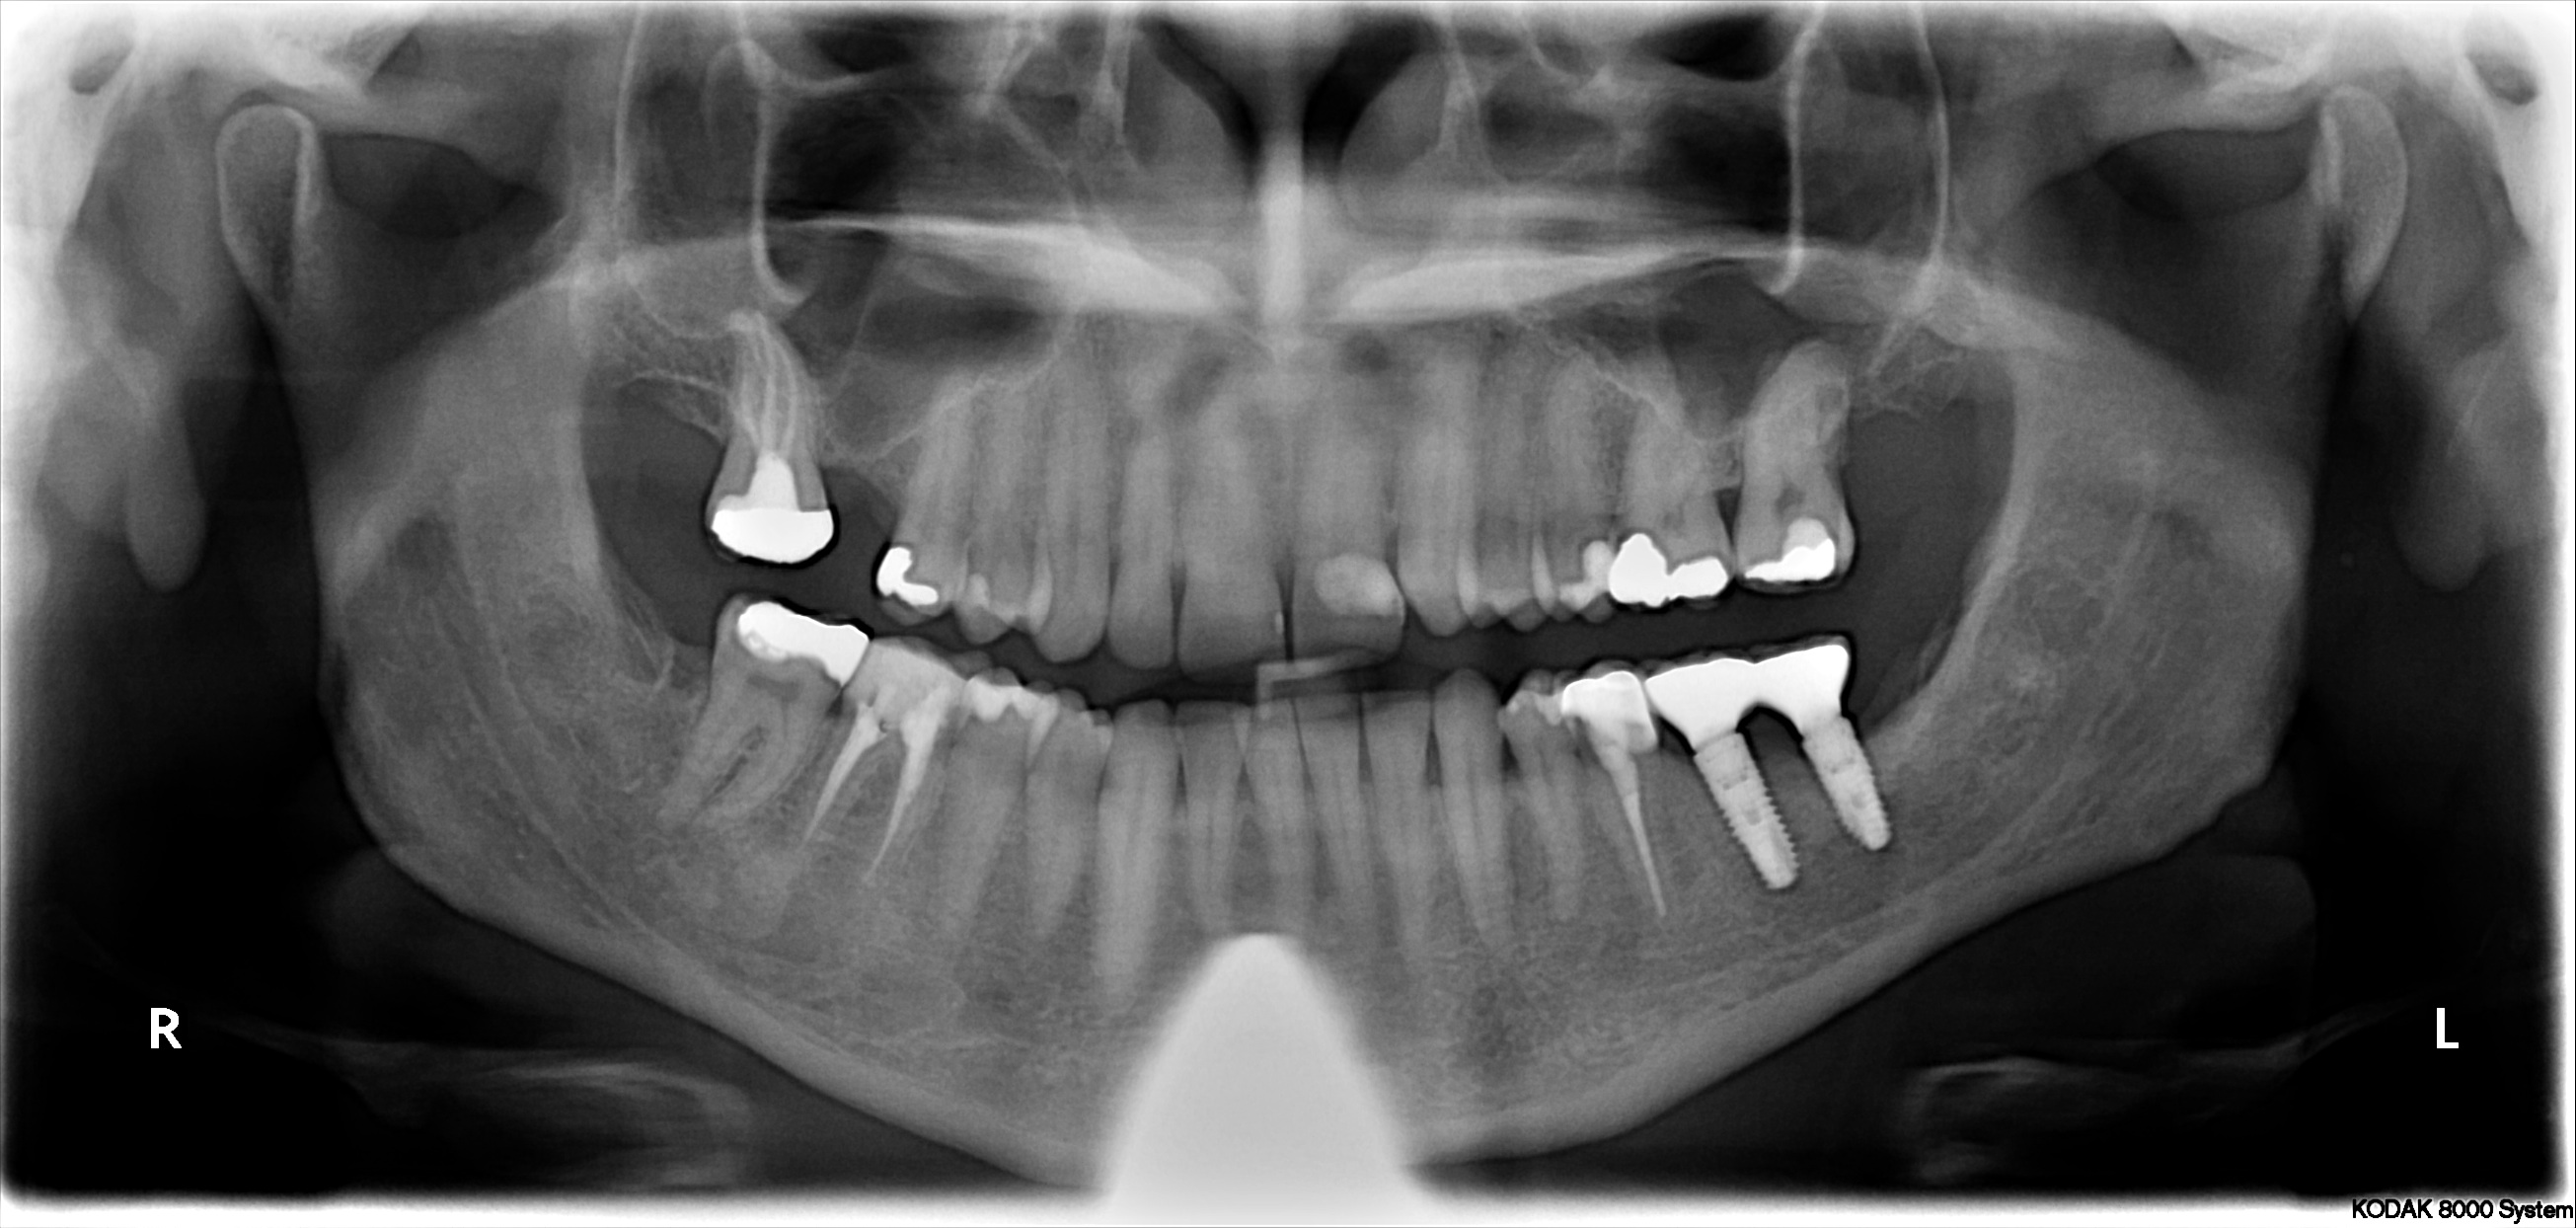

Panoramaaufnahme Veröffentlicht 18. März 2014 am 2610 × 1244 in ZE Planung Panoramaaufnahme Panoramaaufnahme